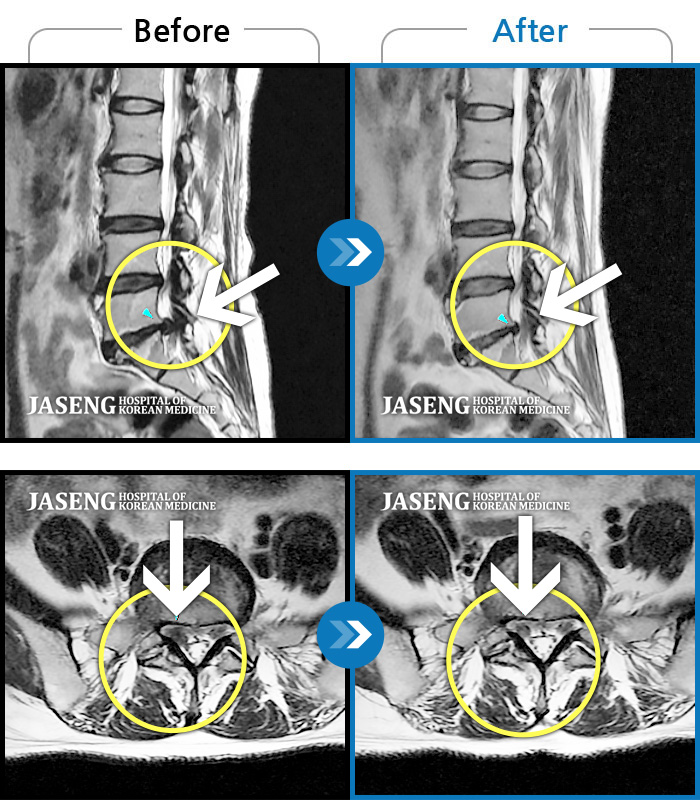

허리디스크

보라매 · 왕오호 원장

허리 통증, 똑바로 서려고 하거나 걸을 때 양쪽 허벅지와 고관절 시큰거림

촬영시기

2017.06.07 ~ 2018.04.17

2018.12.28

조회수 4,169